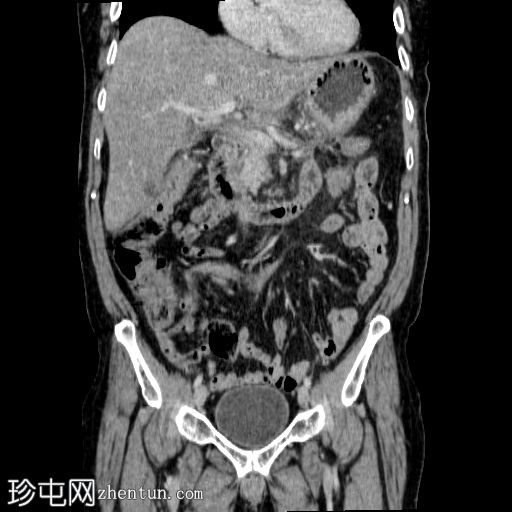

冠状面

非造影

胰体尾弥漫性增大,特征为胰腺实质低强化,无明显坏死区域。

该病灶与以下表现相关:

胰周筋膜平面边界不清的污迹,无明显壁形成、气室、固体碎片或血液产物。

多个亚厘米大小、非特异性的腹主动脉旁淋巴结和肠系膜淋巴结,可能具有反应性。

病变范围如下:

病变横向延伸至左前肾旁间隙,伴有Gerota筋膜增厚。

病变向下延伸至盆腔。

无肠系膜或脾脏血管阻塞的证据。

未见导管扩张或钙化。